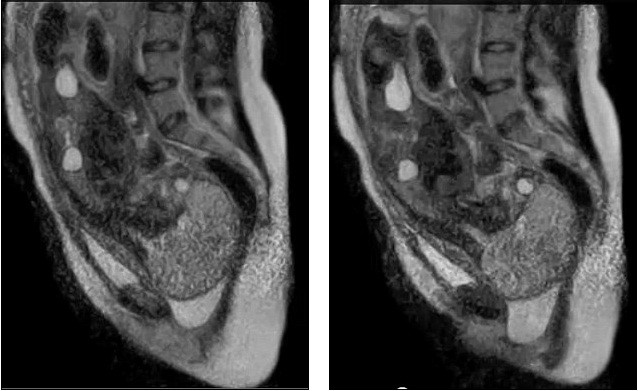

| Ảnh ghi lại quá trình em bé được đẩy dọc theo ống sinh (âm đạo) |

| Tiến trình này được diễn ra theo quy tắc 2 bước tiến và 1 bước lùi. |

Em bé trong đoạn video là con của một bà mẹ 24 tuổi, người tình nguyện tham gia nghiên cứu và đã dành 45 phút bên trong máy MRI để các chuyên gia có thể ghi lại được cảnh tử cung co bóp đẩy em bé xuống ống sinh (âm đạo).

Tuy nhiên, các nhà nghiên cứu đã ngừng ghi hình trước khi em bé xuất hiện bởi trẻ sơ sinh không được tiếp xúc với sóng âm của máy MRI.